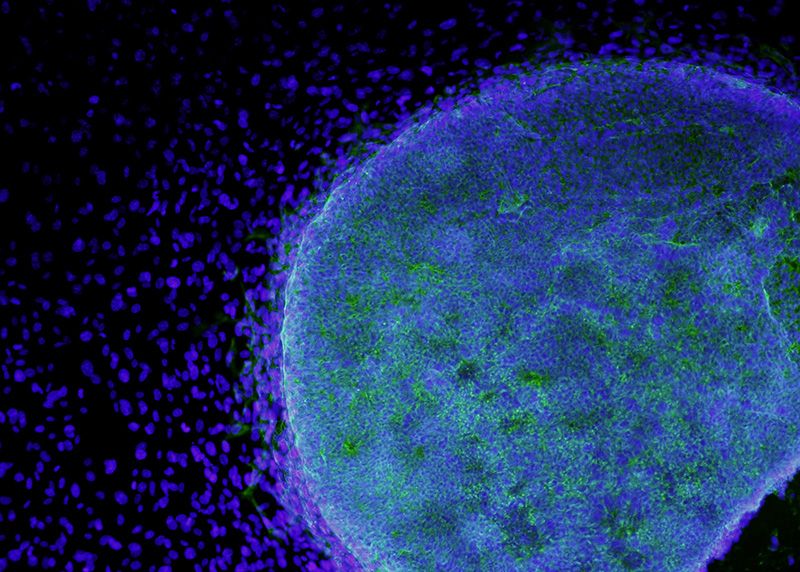

Những người ủng hộ nghiên cứu tế bào gốc ở California đang thúc đẩy một kế hoạch nhằm cứu Viện Nghiên cứu Y học Tái tạo California (CIRM), nơi đang chật vật vận hành chỉ bằng số tiền do chính quyền hỗ trợ. Nhóm ủng hộ đòi hỏi cử tri bang phê duyệt số tiền mang tính sống còn trị giá 5,5 tỷ đô-la Mỹ đối với cơ quan này.

Aaron Levine, nhà nghiên cứu chính sách khoa học tại Viện Công nghệ Georgia ở Atlanta, cho rằng CIRM đã đưa California trở thành trung tâm của lĩnh vực nghiên cứu tế bào gốc trên toàn cầu. “CIRM có vai trò thực sự quan trọng trong việc thúc đẩy quá trình nghiên cứu tế bào gốc, từ khi nó vẫn còn là lý thuyết cho đến khi chứng minh được tính khả thi”, ông nói.

Nhưng Levine không chắc liệu điều đó có đủ để thuyết phục được cử tri tiếp tục ủng hộ cơ quan này không. Chiến dịch thành lập ra CIRM năm 2004, vốn tiêu tốn 34 triệu đô la, đã tranh thủ được sự ủng hộ của những người nổi tiếng như Michael J. Fox và Christopher Reeve, và thuyết phục rằng sáng kiến này có thể áp dụng vào việc chữa trị. Cơ quan này sau đó đã tài trợ cho 55 thử nghiệm lâm sàng, nhưng chỉ một liệu pháp điều trị về tình trạng hiếm gặp về suy giảm miễn dịch kết hợp nghiêm trọng (đôi khi được gọi là chứng bệnh “người bong bóng”) là có khả năng sớm được tung ra thị trường.